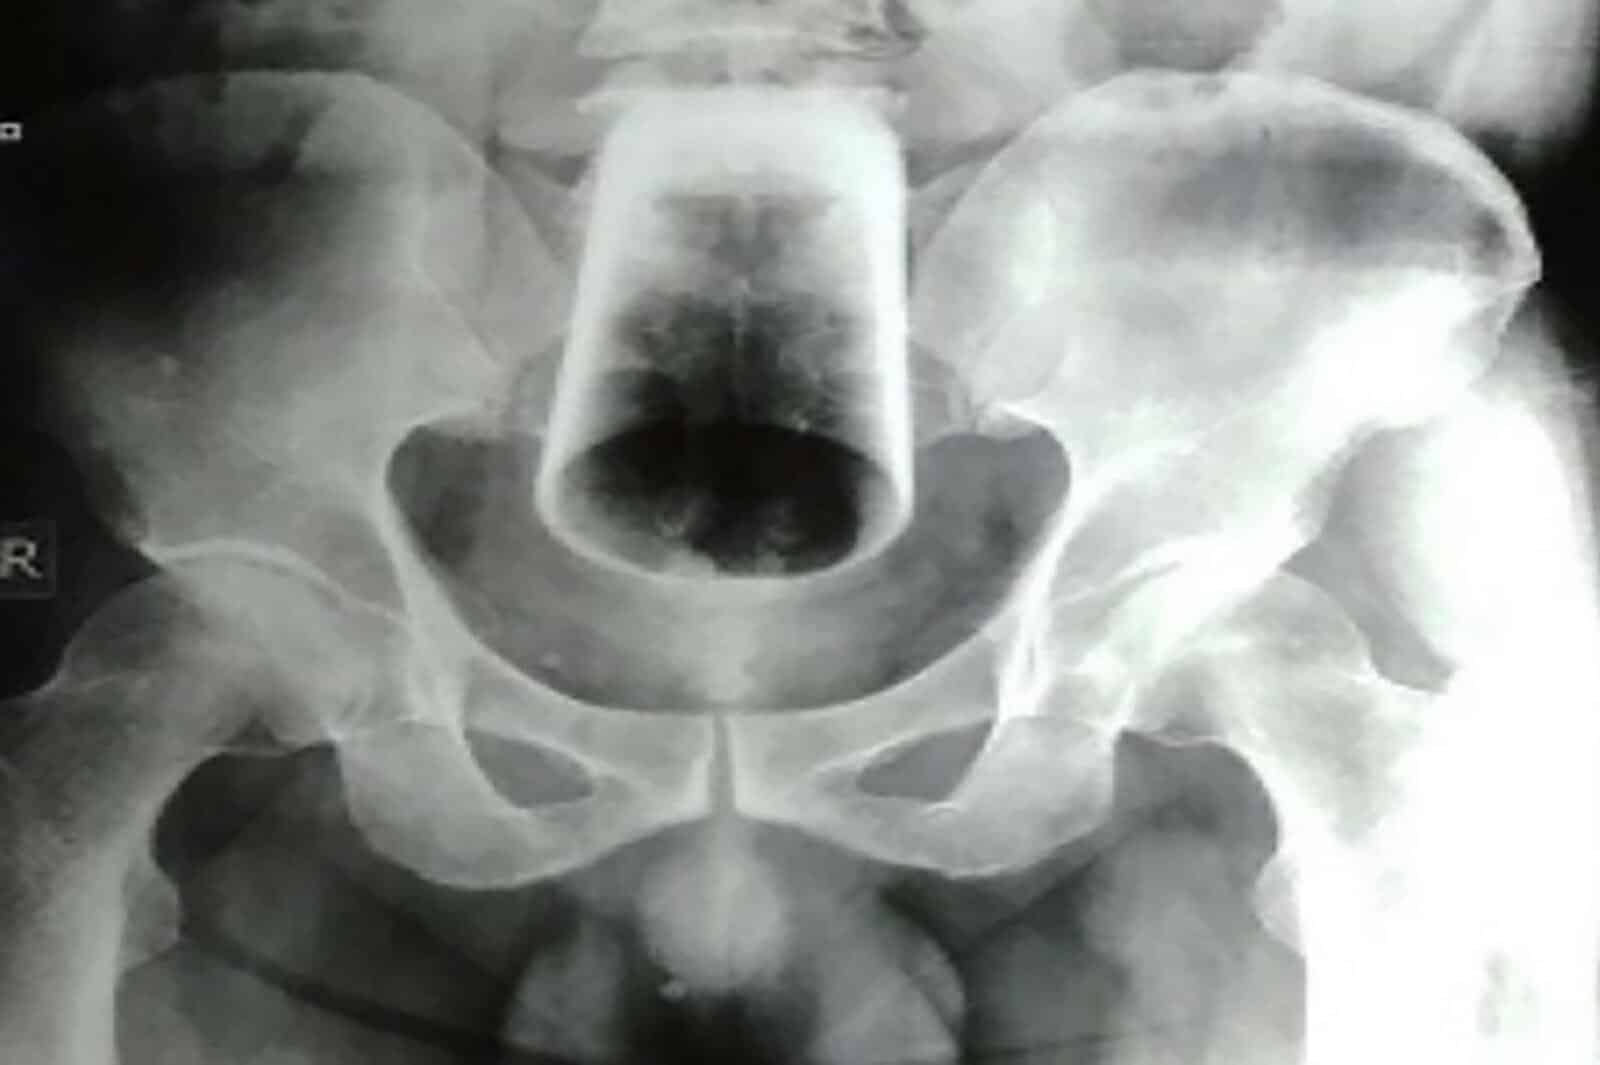

وفي النهاية ، كان على الأطباء فتح بطنه باسم الاستكشاف ، قبل “حلب” الكأس الزجاجي من الرجل عن طريق تدليك أمعائه.

وقال تقرير المجلة: “تمت محاولة الحلب لإخراج الزجاج من خلال فتحة الشرج ، لكن هذا لم ينجح لأن الزجاج كان مرتفعًا ومقلوبًا ومثبتًا بإحكام ومن ثم تم إجراء فغر الأمعاء السيني واستخراج الزجاج.”

وبحسب المجلة كان لدى الرجل شق جراحي في الأمعاء فيما يعرف باسم فغر الأمعاء ، مما سمح للأطباء أخيرًا بالوصول إلى الكأس الزجاجية الموجودة داخل امعائه.